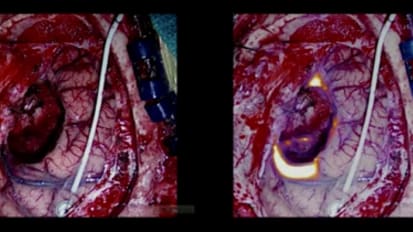

In this video, Robert Lustig, MD, discusses the evolving concept of re-irradiation of primary brain tumors by reviewing three relevant clinical studies and a recent experience at the Roberts Proton Therapy Center at Penn Medicine. Dr. Lustig describes the studies, which involved the retreatment of glioblastomas with bevacizumab in combination with conventional fractionated, stereotactic and hypofractionated radiotherapy, with a focus on respective survival and time to progression benefits. His discussion of proton therapy examines a single case involving the retreatment of a brainstem tumor with pencil beam scanning.